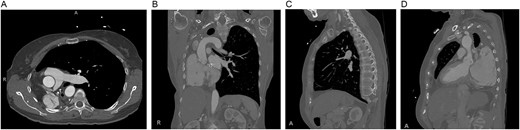

Preoperative computed tomography of the chest. Axial (A), coronal (B) and sagittal (C, D) views demonstrating displacement of the heart and left lung into the right hemithorax.